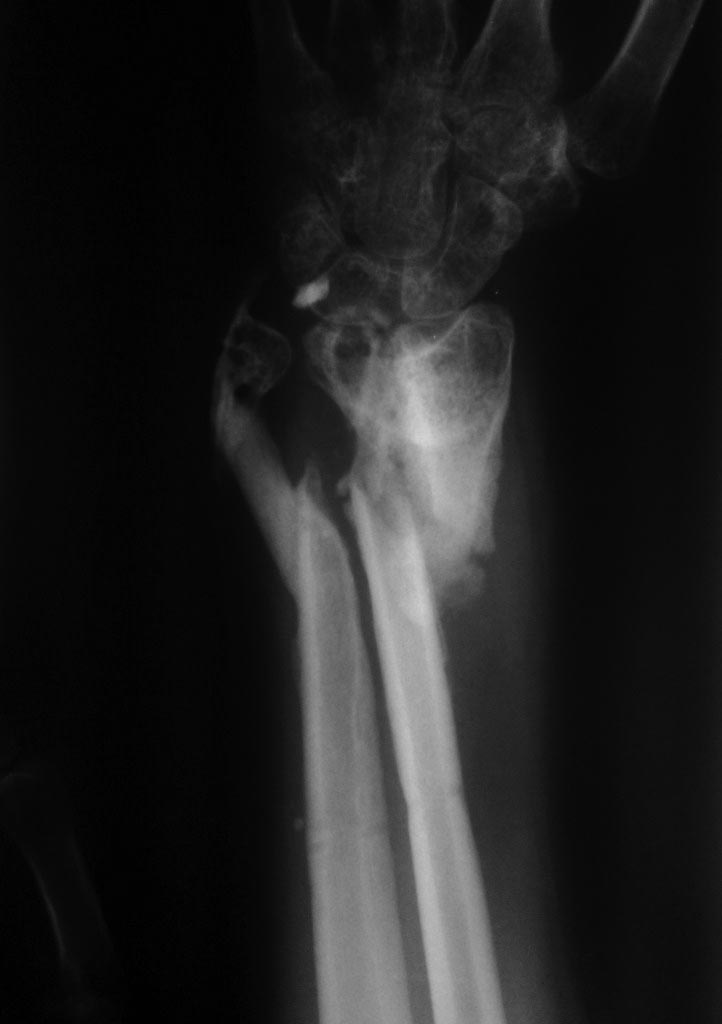

Re: неправильно сросшийся перелом предплечья

Хотелось бы и на рентгенограмму в прямой проекции взглянуть.

Снимки досылаю. Спасибо

План хороший, только для достижения положительного результата нужно будет еще что-нибудь делать с локтевой костью (либо остеотомию с остеосинтезом, либо резекцию головки), иначе будут проблемы с функцией конечности. Кстати КТ производилось или нет, а то есть смутные подозрения на ложный сустав лучевой кости.

Спасибо что потратили свое время!!! Пациентка все осознала, сотрудничает с врачами и выполняет все рекомендации. Кожа в области перелома зажила. При более детальном обследовании все-таки имеется тугой ложный сустав. Как на Ваш взгляд лучше подойти к перелому- с передней или задней поверхности?